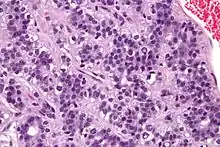

| Micrograph of an adenomyoepithelioma. H&E stain. | |

An adenomyoepithelioma of the breast is a rare tumour in the breast composed of glandular elements (adeno-) and myoepithelial cells. It is usually benign;[1] however, there are reports of malignant behaviour.[2]

The histomorphologic appearance can mimic invasive ductal carcinoma, the most common type of invasive breast cancer.